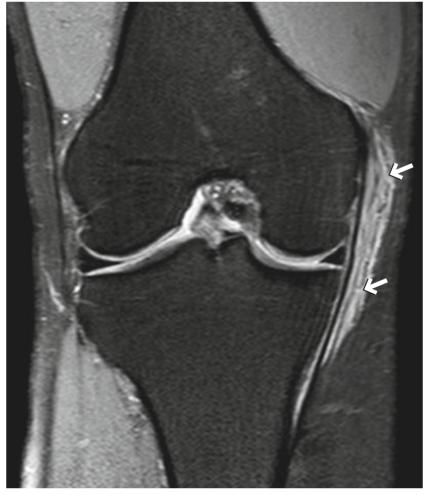

在1级MCL撕裂中,可以看到线性高信号,代表由于扭伤或劳损引起的韧带纤维水肿(图5.7)。然而,这种影像学发现也可以在内侧半月板撕裂和膝关节炎中发现。

图5.7的一级撕裂(拉伤)。一名20多岁的男子在演讲前一天滑雪受伤。冠状面FS PDWI显示沿MCL表层呈线性高信号,代表由于拉伤引起的水肿(箭头)